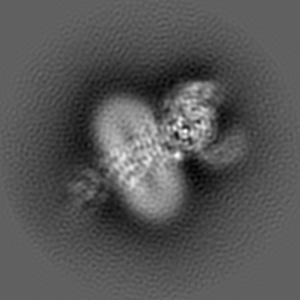

Cryo-EM structure of parathyroid hormone receptor type 1 in complex with a long-acting parathyroid hormone analog and G protein

Single-particle4.0 Å